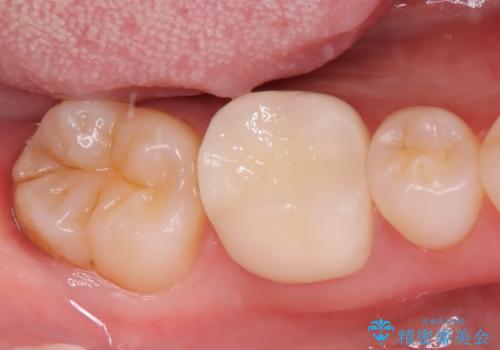

虫歯 〈セラミックインレー〉

- 初診時にお口の中をチェックしたところ虫歯があり、大きさから部分的な詰め物のお話をしました。材料の特性を説明し、再び虫歯になりにくいセラミックインレーを選択されました。

セラミックインレー接着時にはラバーダム防湿を行いました。